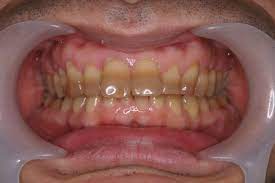

変色とは、主に加齢による歯の黄ばみです。

歯は象牙質と呼ばれる黄色みのある内層と白く透明なエナメル質と呼ばれる外層で包まれています。

加齢によりエナメル質は摩耗し薄くなり象牙質が透けて見えるようになり象牙質が透けて見えることにより黄色く映ります。

また、象牙質自体も加齢により黄色く変色します。